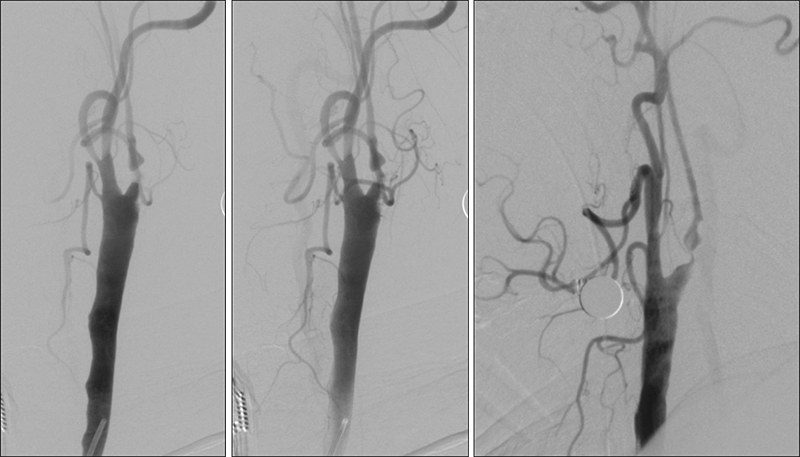

Εικόνα 7: Παρότι η αριστερή πλευρά είναι συμπτωματική, η παρουσία προσφάτων θρόμβων στον αριστερό καρωτιδικό βολβό αποτελεί αντένδειξη άμεσης αντιμετώπισης. Αποφασίσθηκε να τεθεί ο ασθενής σε θεραπευτικά επίπεδα αντιπηκτικής αγωγής με ηπαρίνη. Ταυτόχρονα, αντιμετωπίσθηκε πρώτα η δεξιά καρωτιδική στένωση με τοποθέτηση stent τύπου closed-cell με σύστημα προστασίας εμβόλων Spider.

Εικόνα 8 και 9: Έγχυση στην αριστερή κοινή καρωτίδα, μία εβδομάδα αργότερα υπό αντιπηκτική και αντιαιμοπεταλιακή αγωγή. Βλέπουμε βελτίωση της εικόνας στον αριστερό καρωτιδικό διχασμό. Συγκεκριμένα φαίνεται απορρόφηση των θρομβωτικών στοιχείων, με ελαφρά βελτίωση της ροής προς την μέση εγκεφαλική.

08

09

Εικόνα 10: Τοποθέτηση του εγγύς συστήματος προστασίας MOMA με διάταση του περιφερικού μπαλονιού στην αρχή της αριστερής έσω καρωτίδος.

10

Εικόνα 11: Αποκατάσταση της στενώσεως του αριστερού καρωτιδικού βολβού με  τοποθέτηση stent τύπου closed-cell.

11

Εικόνα 12 και 13: Κατά την ενδοκράνια προσθιοπίσθια και πλάγια προβολή της αριστερής κοινής καρωτίδος μετά την επέμβαση, παρατηρείται σημαντική αιμοδυναμική βελτίωση με αναστροφή της ροής στην αριστερή πρόσθια εγκεφαλική αρτηρία που είναι πλέον ομόδρομη.

12

13